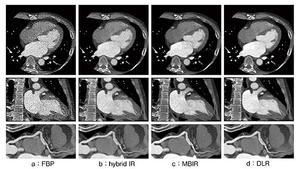

最新の心臓CT技術:心筋評価の最前線

加藤 真吾(横浜市立大学大学院医学研究科放射線診断学教室)

高精細・AI 技術による治療戦略の変化

河合 秀樹(藤田医科大学医学部循環器内科)